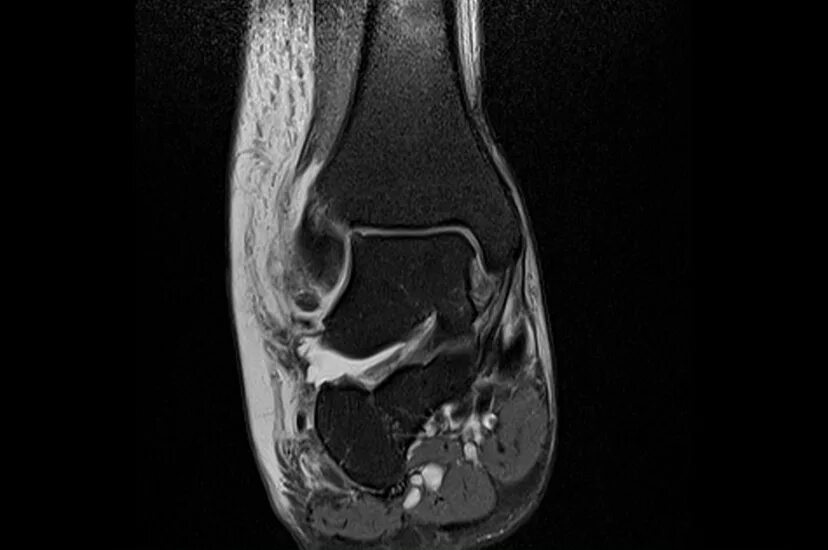

Мрт суставов химки